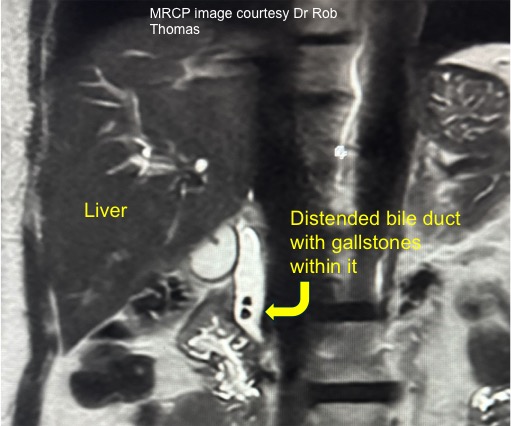

Occasionally, other tests may be required, such as an MRI scan (referred to as MR cholangio-pancreatography or MRCP), CT scan, or radio-isotope tests such as HIDA scans. An MRCP will show the anatomy of the liver and the gall bladder, the bile duct, as well the surrounding organs such as the pancreas (see illustration).

What if I have a stone in my bile duct?The adjacent picture is of an MRI scan that shows stones in the gall bladder and in the bile duct. If stones in the bile duct are identified beforehand, then they can be removed through an endoscope (at an ERCP) before the operation to remove the gall bladder.